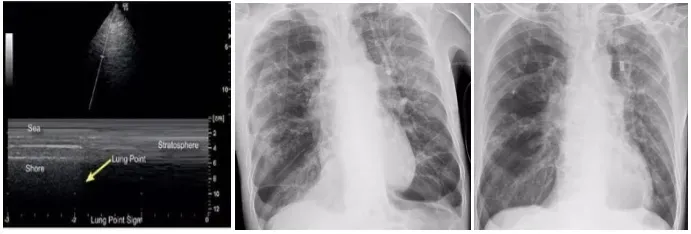

67岁的患者因“心前区疼痛1天”入院,被诊断为冠状动脉粥样硬化性心脏病、急性前壁心肌梗死,心功能Ⅳ级,同时还伴有慢性阻塞性肺疾病急性加重期以及慢性肺源性心脏病,病情复杂危重。入院后,患者因心衰加重转入重症医学科,持续接受无创呼吸机辅助呼吸。经过一段时间的治疗后,患者的病情突然恶化,气短症状急剧加重,同时伴有胸部憋闷、口唇发绀等症状。复查血气分析显示,其P02降至46mmHg,情况万分危急。重症医学科团队迅速行动,立即为患者进行气管插管并使用呼吸机辅助呼吸,随后紧急开展床旁肺部超声检查。检查结果显示,高卧位下右肺第二肋间胸膜滑动症消失,呈现出平流层征——这是典型的气胸表现。

明确病因后,医护人员迅速调整呼吸机参数,给予高浓度氧疗。经过紧张的救治,当晚复查床旁肺部超声,惊喜地发现高卧位右侧第二肋胸膜滑动症重新出现,这意味着气胸情况得到了改善。第二天复查胸片,结果显示右侧气胸较前明显吸收,患者脱离了生命危险。